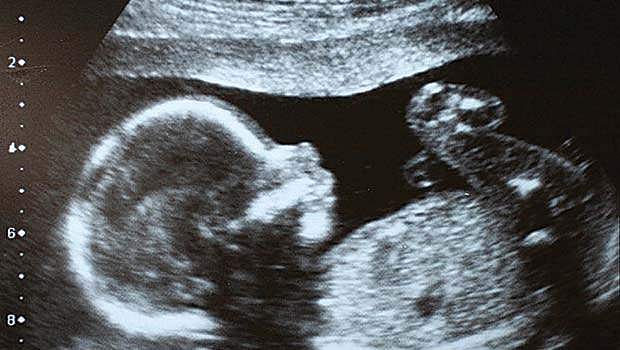

கருவிலேயே அழிக்கப்படும் பெண் சிசுக்கள்: துணைபோகும் மருத்துவர்கள்

தமிழகத்தில் பெண் சிசுக்கள் கருவிலேயே அழிக்கப்படுவது அதிகரித்துள்ளது.

தமிழகத்தில் பெண் சிசுக்கள் கருவிலேயே அழிக்கப்படுவது அதிகரித்துள்ளது. இந்த மாபாதகச் செயலுக்கு ஸ்கேன் மையங்களும், மருத்துவர்களும் துணைபோவது அதிர்ச்சியை எற்படுத்தியுள்ளது. இந்தியாவில் ஆண் சிசு இறப்புடன் ஒப்பிடுகையில், பெண் சிசுவின் இறப்பு விகிதம் 75 சதவீதம் அதிகம். உலகின் பல நாடுகளிலும் 100 ஆண் குழந்தை பிறக்கும்போது, 105 பெண் குழந்தைகள் பிறக்கின்றனர். ஆனால், இந்தியாவில் 100 ஆண்களுக்கு 90-க்கும் குறைவான பெண் குழந்தைகள்தான் பிறக்கின்றனர். இந்தியாவில் ஒவ்வொரு நாளும் 2,000 பெண் சிசுக்கள் சட்டத்துக்குப் புறம்பாக கருவிலேயே கொலை செய்யப்படுவதாகக் கூறுகிறது ஐக்கிய நாடுகள் சபையின் அறிக்கை. இதனால் ஆண், பெண் விகிதாசாரம் அதிகளவில் வேறுபடுகிறது.

17 ஸ்கேன் மையங்கள் "சீல்'

மருத்துவ வசதி முன்னேறி, நவீன அல்ட்ரா சவுண்ட் ஸ்கேன் முறை வந்தபிறகு, கர்ப்பிணியின் வயிற்றில் இருக்கும் குழந்தை ஆணா, பெண்ணா என எளிதில் தெரிந்துகொண்டு பெண் குழந்தைகளை சர்வ சாதாரணமாக கருக்கலைப்பு செய்து அழித்து வருகின்றனர்.

தமிழகத்தில் ஆண்டுக்கு 5,000 பெண் சிசுக்கள் கருவிலேயே கொல்லப்படுவதாக ஸ்கேன் மையங்கள் தொடர்பான விசாரணையின்போது உச்சநீதிமன்றத்தில் தெரிவிக்கப்பட்டுள்ளது. ஆனால், இந்த எண்ணிக்கை லட்சத்தைத் தாண்டும் என்கின்றனர் சமூக ஆர்வலர்கள்.